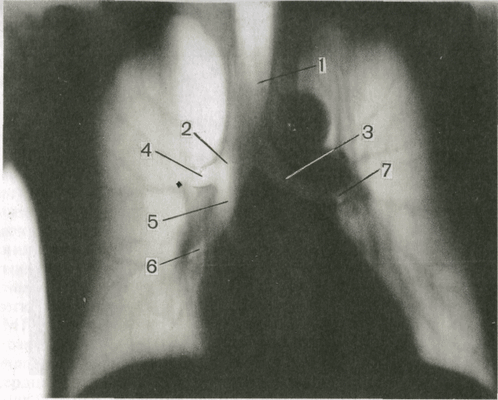

На обзорной рентгенограмме в прямой проекции (рис 1) почти на всем протяжении вырисовываются верхние 5-6 пар ребер. У каждого из них можно выделитьтело, передний и задний концы. Нижние ребра частично или полностью скрыты за тенью средостения и органов, расположенных в поддиафрагмальном пространстве. Изображение передних концов ребер обрывается на расстоянии 2-5 см от грудины, так как реберные хрящи не дают различимой тени на снимках. У лиц старше 17-20 лет в этих хрящах появляются отложения извести в виде узких полосок по краю ребра и островков в центре хряща. Их, разумеется, не следует принимать за уплотнения легочной ткани. На рентгенограммах легких имеется также изображение костей плечевого пояса (ключиц и лопаток), мягких тканей грудной стенки, молочных желез и органов, расположенных в грудной полости (легкие, органы средостения).

Рис.1 Передняя обзорная рентгенограмма органов грудной полости и схема к ней.

1 — передний конец ребра; 2 — трахея и главные бронхи; 3 — тело ребра; 4 -правая нижнедолевая артерия; 5 — диафрагма; 6 — задний конец ребра; 7 -корень левого легкого; 8 — контур левой молочной железы.

Оба легких на обзорной прямой рентгенограмме видны раздельно; они образуют так называемые легочные поля, которые пересекаются тенями ребер. Между легочными полями находится интенсивная тень средостения. Легкие здорового человека заполнены воздухом, поэтому на рентгенограмме представляются очень светлыми. Легочные поля имеют определенную структуру, которую называют легочным рисунком. Он образован тенями артерий и вен легких и в меньшей степени окружающей их соединительной тканью. В медиальных отделах легочных полей, между передними концами II и IV ребер, вырисовывается тень корней легких. Главным признаком нормального корня является неоднородность его изображения: в нем можно различить тени отдельных крупных артерий и бронхов. Корень левого легкого расположен немного выше корня правого, его нижняя (хвостовая) часть скрывается за тенью сердца.